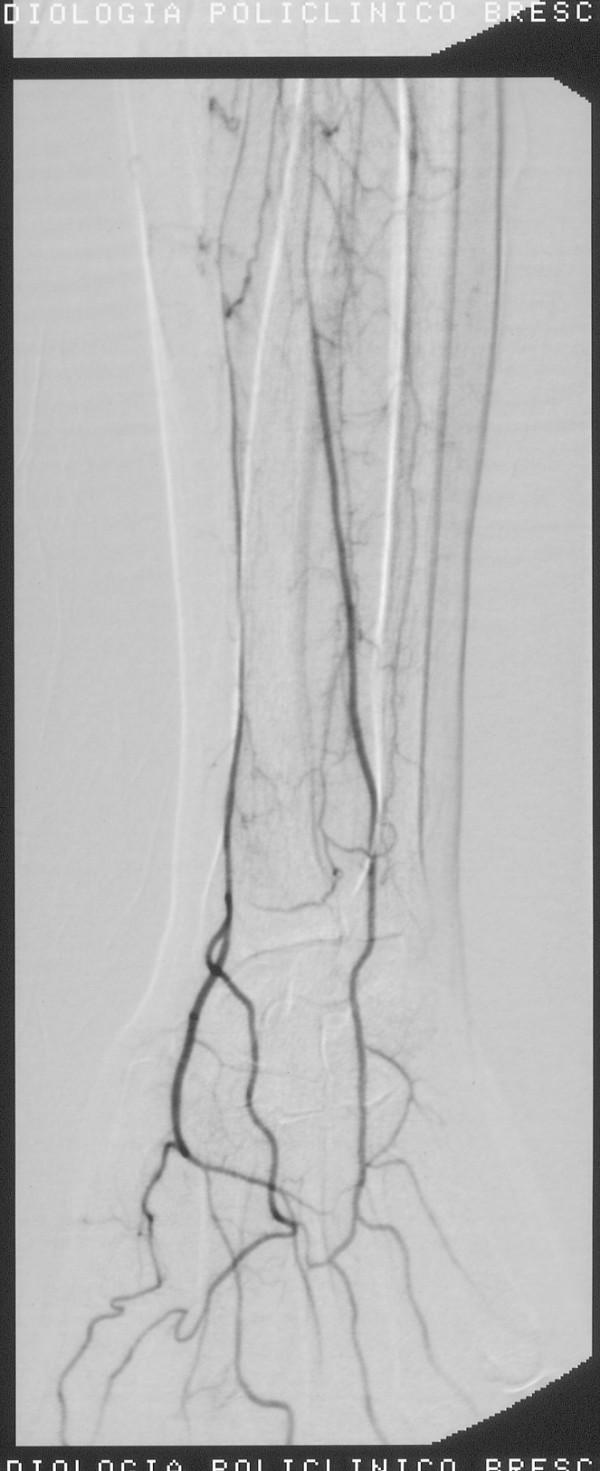

Angiography revealed progressive reduction in size of the axillary artery and right humeral artery stenosis with right segmental occlusions and multiple hypertrophic collateral circulations at the elbow joint. At the level of the right forearm was recognizable only the radial artery, decreased in size. Does not recognize the ulnar, interosseous artery was thin. To the left showed progressive reduction in size of the distal subclavian and humeral artery, determined by multiple segmental steno-occlusion with collateral vessels serving only a thin hypotrophic interosseous artery.Arteriographic findings were compatible with systemic drug-induced disease. The immediate implementation of thrombolysis, continued for 26 hours, with heparin in continuous intravenous infusion and subsequent anticoagulant therapy allowed the gradual disappearance of the symptoms with the reappearance of peripheral pulses.

CONCLUSION

Angiography showed regression of vasospasm and the resumption of flow in distal vessels. The patient had regained sensitivity and motility in the upper limbs and bilaterally radial and ulnar were present.

血管造影显示腋动脉和右肱动脉管径逐渐减小,右侧节段性闭塞,肘关节处有多个肥厚的侧支循环。在右前臂水平仅可识别桡动脉,其管径减小。未识别出尺动脉,骨间动脉变细。左侧显示锁骨下动脉远端和肱动脉管径逐渐减小,由多个节段性狭窄闭塞所致,侧支血管仅供应一条细小的发育不良的骨间动脉。血管造影结果与全身性药物性疾病相符。立即实施溶栓治疗,持续26小时,持续静脉输注肝素并随后进行抗凝治疗,症状逐渐消失,外周脉搏重新出现。

结论

血管造影显示血管痉挛消退,远端血管血流恢复。患者上肢恢复了感觉和活动能力,双侧桡动脉和尺动脉均存在。